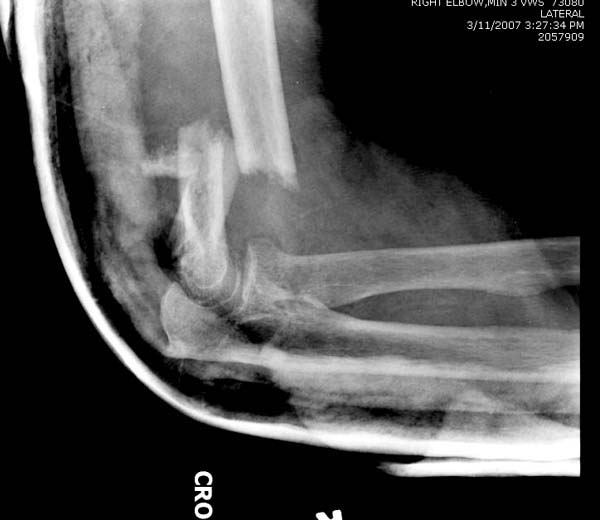

Из представленнего материала видно, что между снимками нет разницы.

Отсутствует репозиция не только медиального, а также латерального

мыщелка. На боковом снимке мыщелок расположен спереди, а прямом головка

луча упирается в край мыщелка, что означает ротацию. Отсутствует

компрессия между мыщелками, а один шуруп не смог удержать медиальную

сторону, которая при первом же движении рассыпалось.

Ошибка в фиксации привела к дополнительным проблемам, теперь, кроме

плеча, надо заниматься с локтевым отростком и невритом. Доступ обычно из